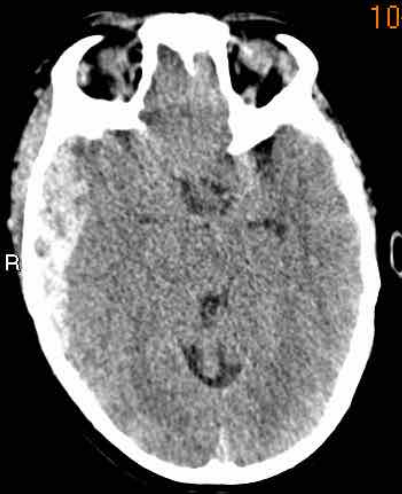

下图显示了外侧裂蛛网膜下腔(黄色箭头)的高密度血液。

注意右侧枕部的皮下出血(蓝色箭头)。

这是一种对冲伤。